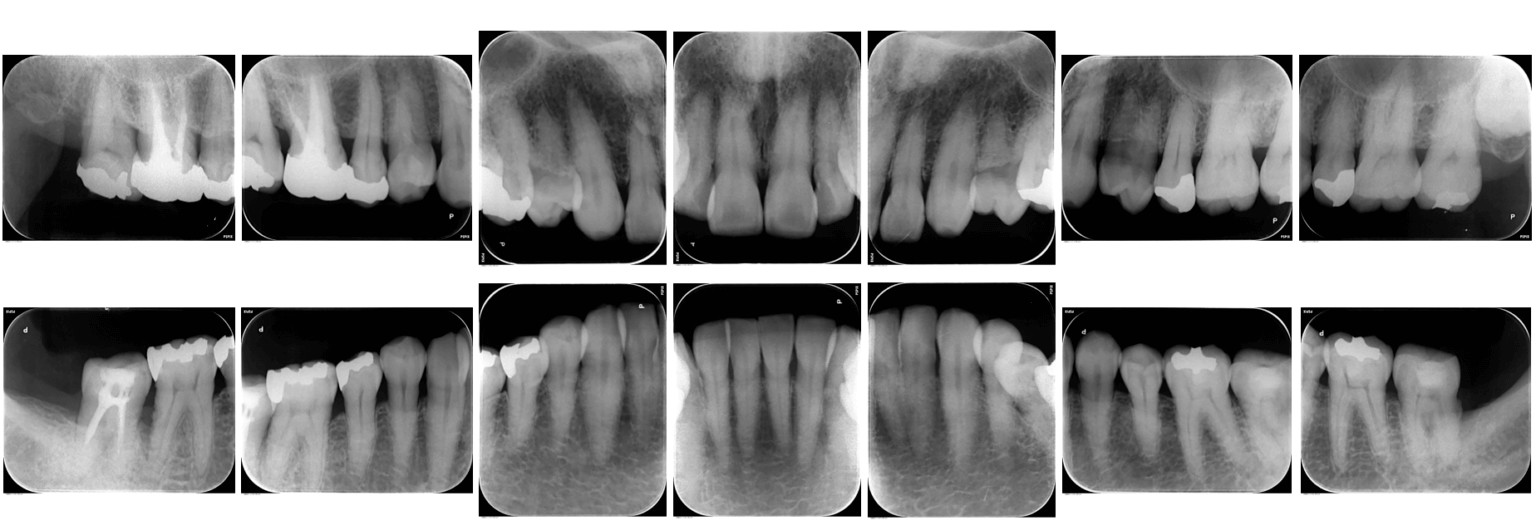

③レントゲン検査

レントゲンは、歯やその周りの組織の状態を詳しく調べるために非常に重要な検査です。まず歯の周りの骨の状態を確認していきます。歯を支える骨がどのくらい健康で、どのくらいの高さがあるかを確認します。歯周病が進行すると、骨が徐々に失われてしまうため、レントゲンを用いて診断します。レントゲンでは歯茎はうつらず、骨が写ってくるため目視では確認できない、歯の根や歯の間の問題を発見します。これには、歯根の周囲の感染や、歯の根に生じた損傷などが含まれます。そのレントゲンの結果をもとに、最適な治療方法を決定していきます。